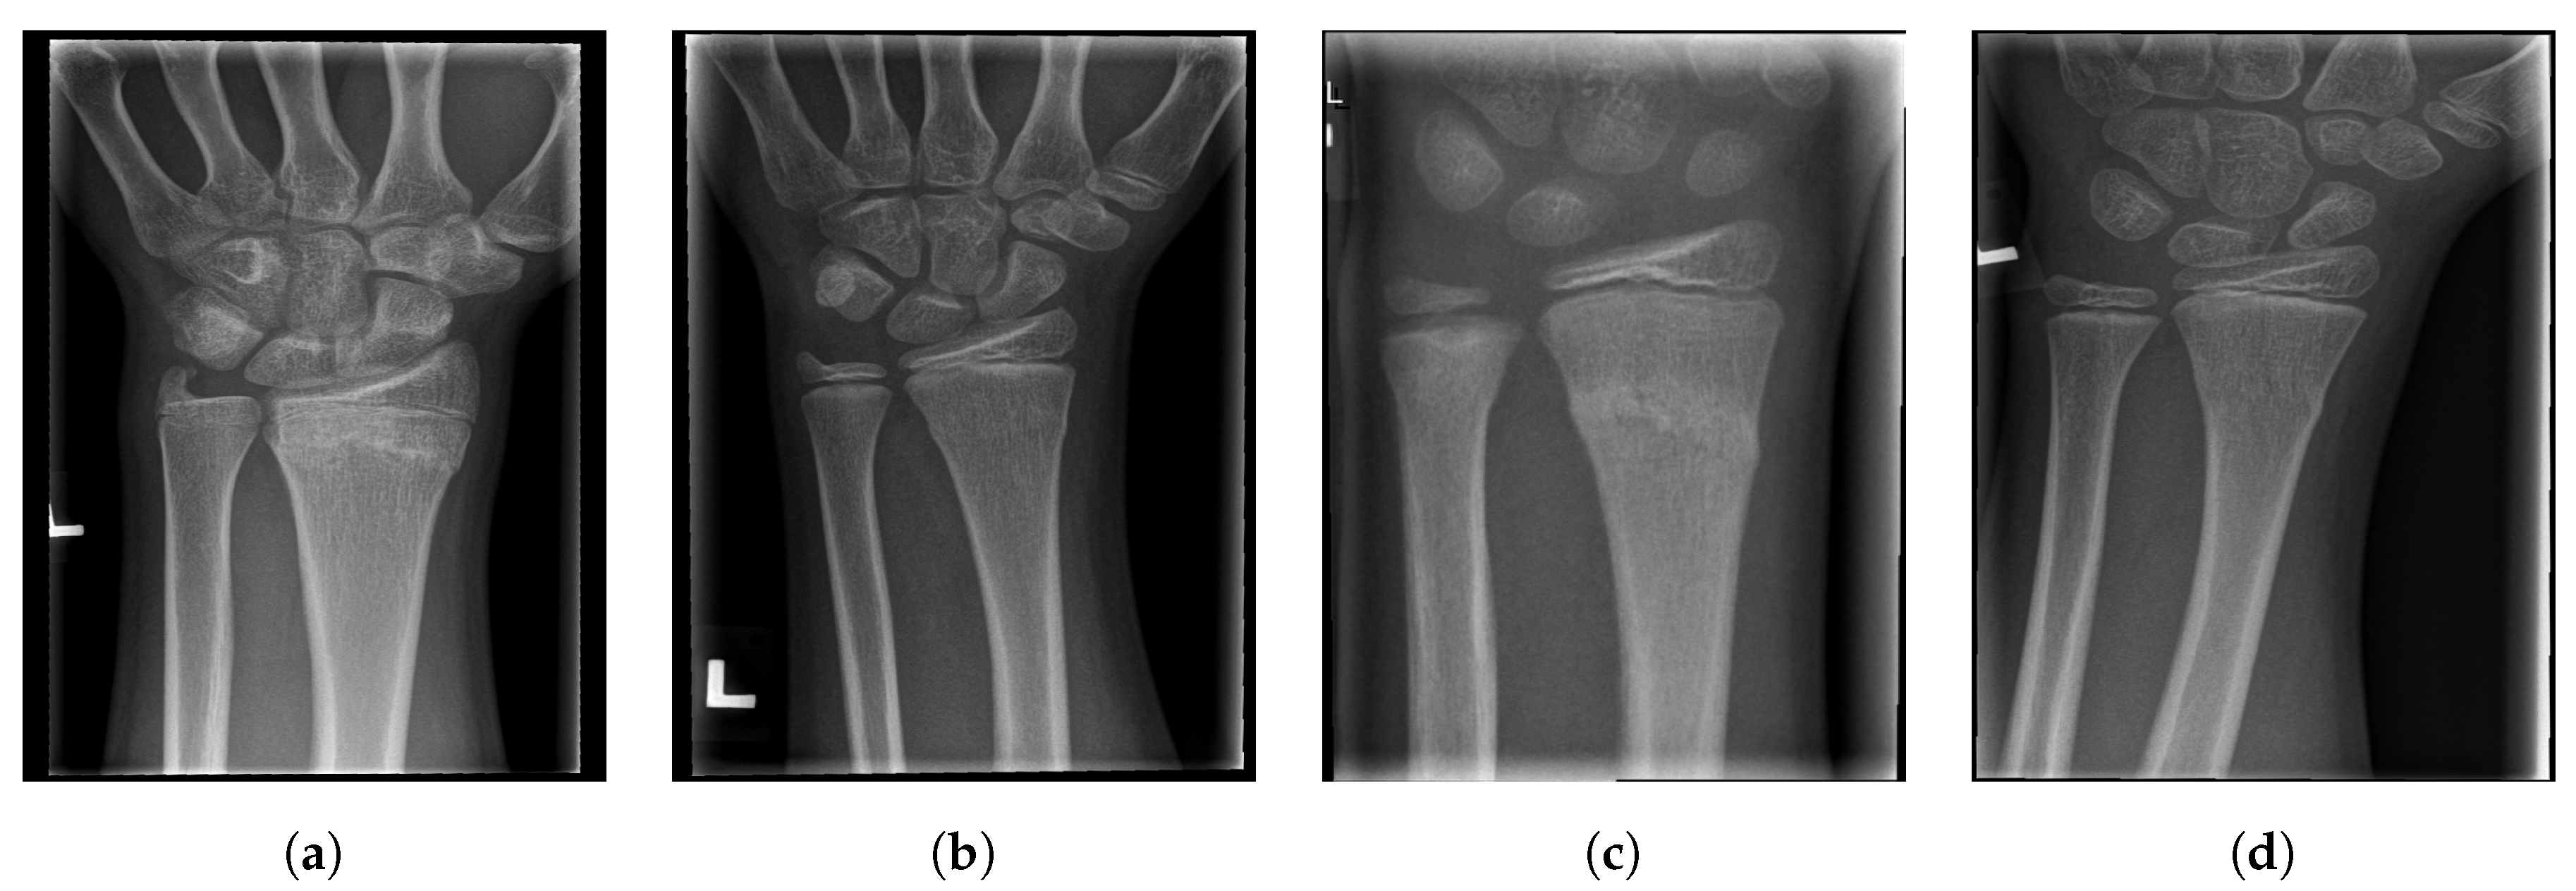

For illustration, four images from each class (TP, TN, FP, and FN) are given in Figure 17, Figure 18, Figure 19 and Figure 20.

Examples from the true negative (TN) performance metric class.

Figure 19.

Examples from the false positive (FP) performance metric class.

Figure 20.

Examples from the false negative (FN) performance metric class.